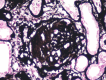

Diabetic kidney disease is a very prevalent complication in the context of type 2 diabetes. However, there is evidence showing a high variability in diagnosis when a kidney biopsy is performed. We present a case of a woman with a diagnosis of diabetic kidney disease, systemic arterial hypertension, obesity, and a high risk of progression of chronic kidney disease who presented with a sudden onset nephrotic syndrome and rapidly progressive deterioration of renal function. Kidney biopsy revealed pauci-immune extracapillary glomerulonephritis with acute thrombotic microangiopathy and class IIa diabetic nephropathy. Antineutrophil cytoplasmic antibodies (ANCA) and low complement were detected. The patient received treatment based on plasma exchanges, steroids with methylprednisolone and prednisone and intravenous cyclophosphamide with improvement of renal function. In conclusion, expansion of kidney biopsy criteria in patients with a diagnosis of type 2 diabetes is mandatory to provide adequate treatment and prognosis in the context of a high prevalence of alternative or concomitant disease.